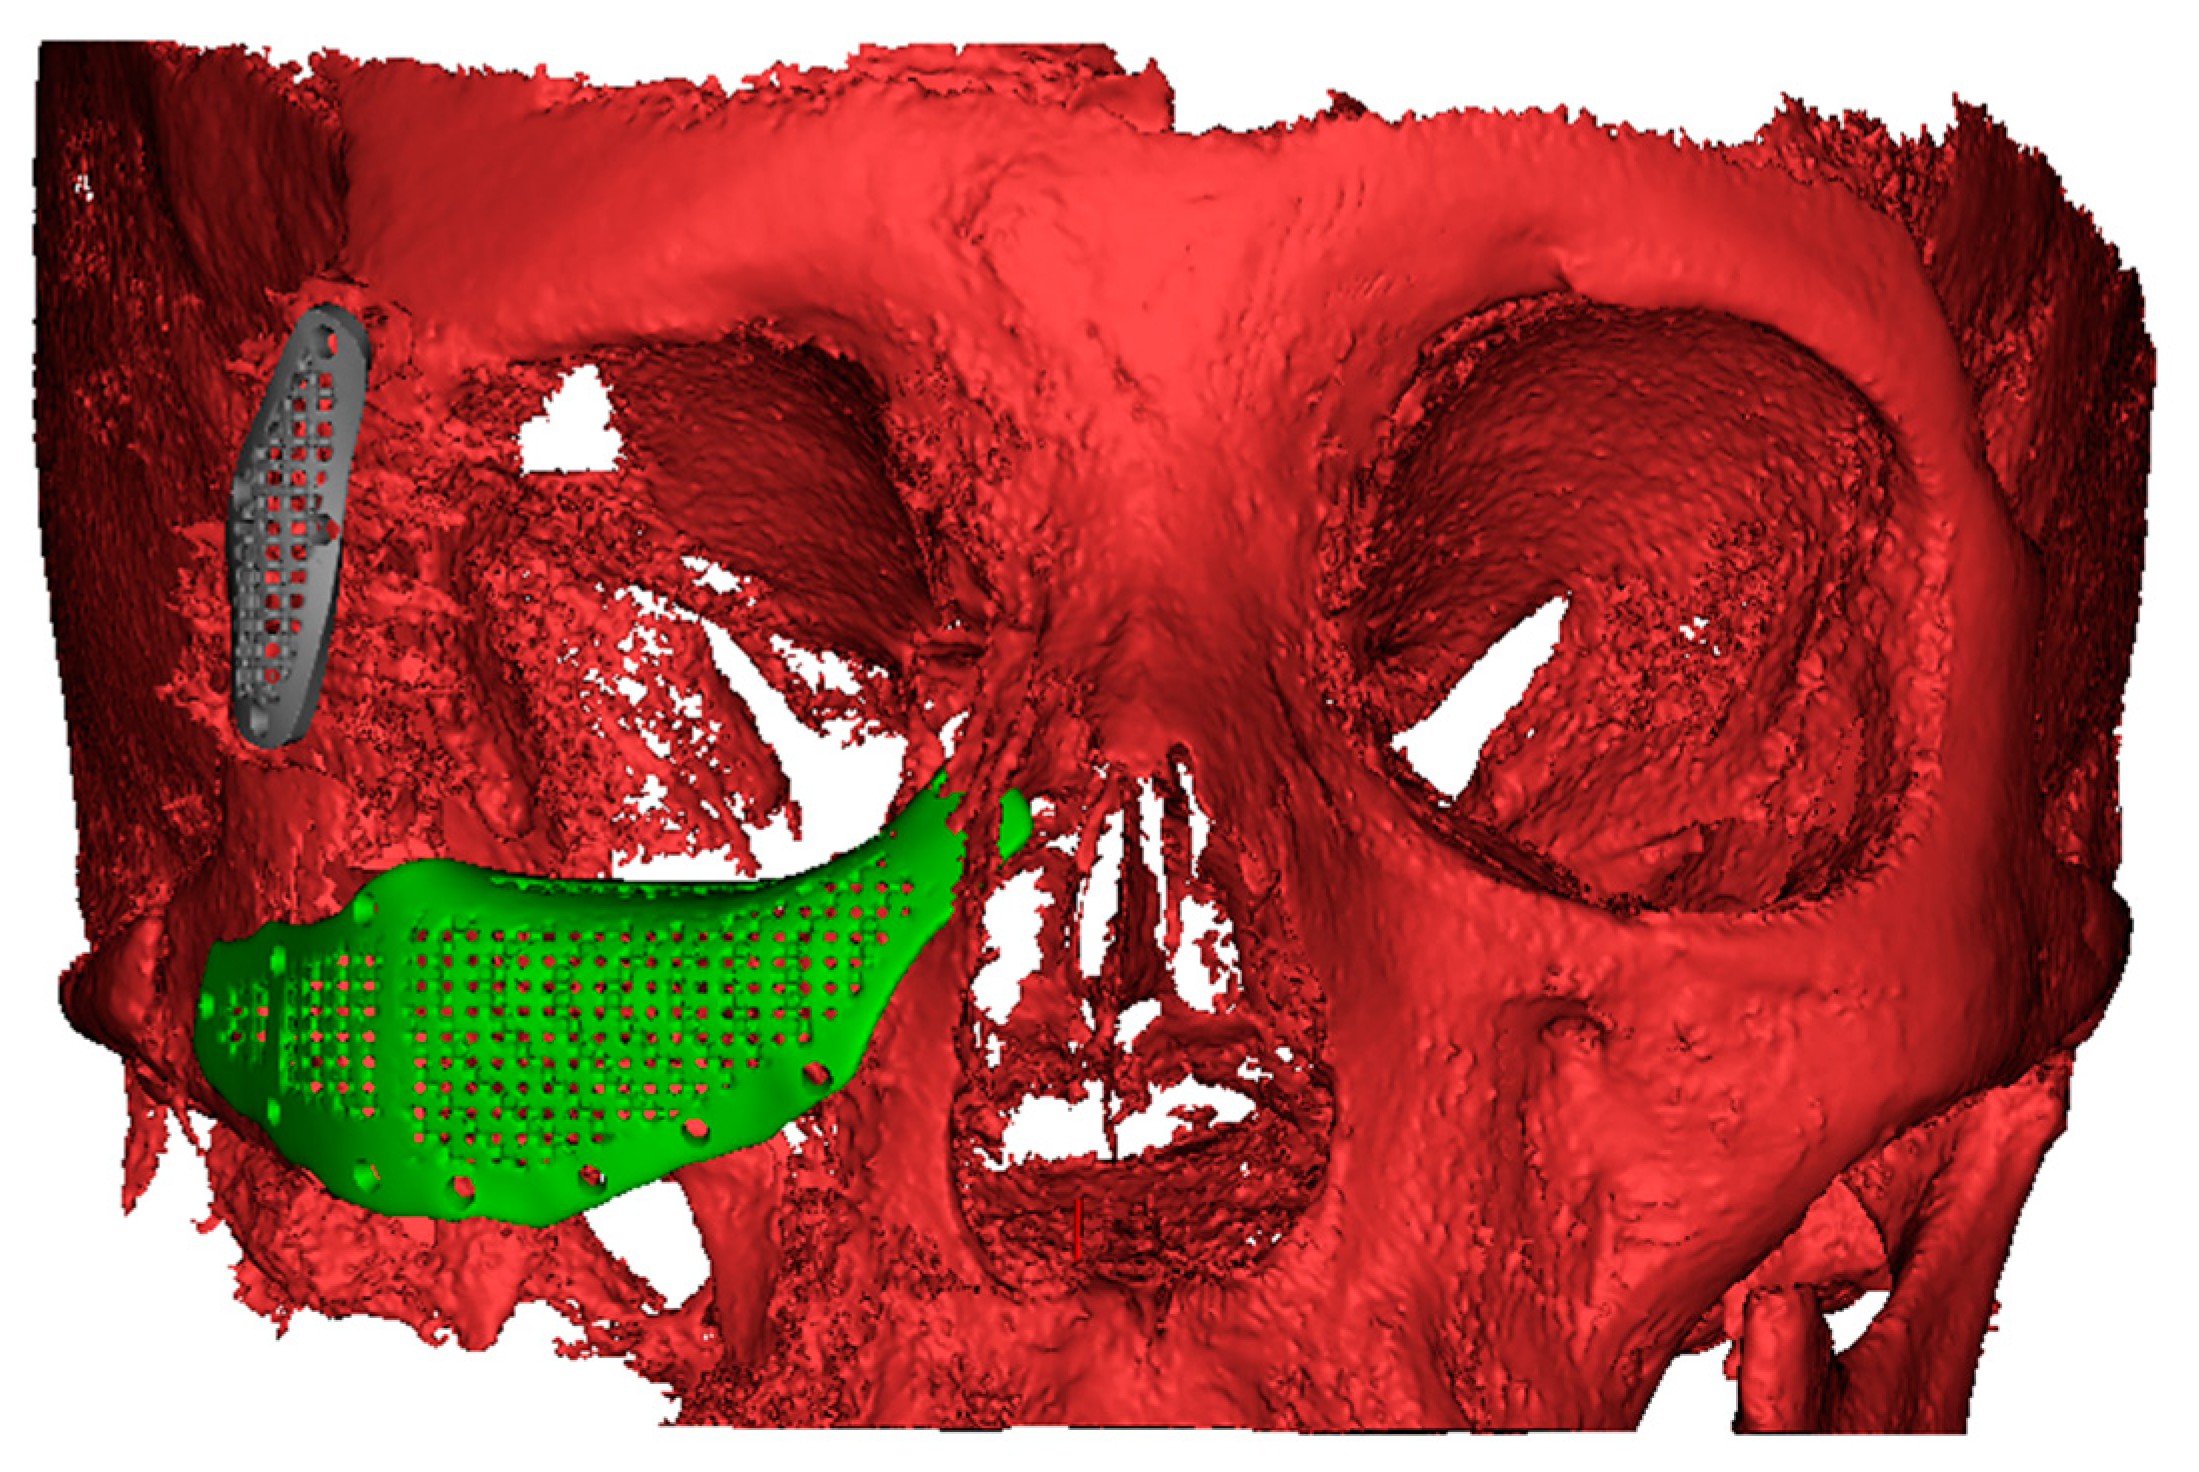

2.4. Virtual Planning of Patients-Specific Implants

2.5. Manufacturing of Patient-Specific Implants and Surgical Procedure